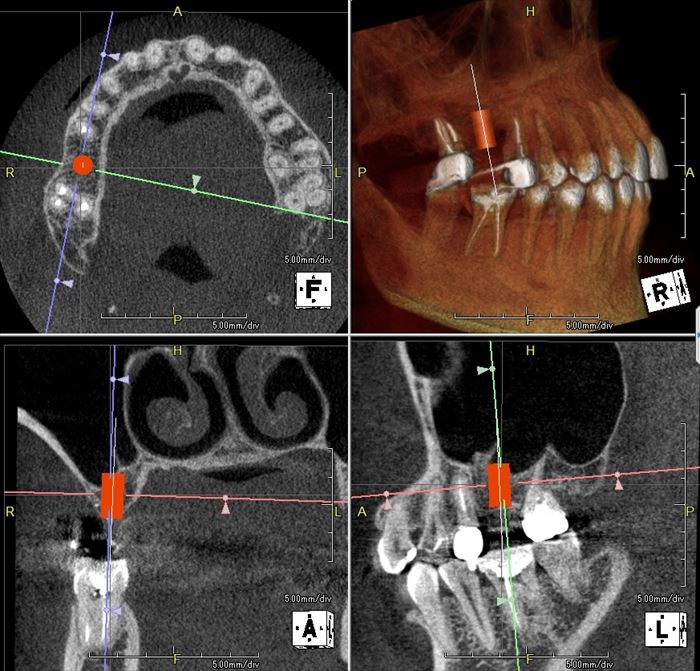

オフィス内の歯科用CTにてインプラントシミュレーションを行います。

CTデータと重ね合わせ、模型上でインプラント埋入位置・角度を決定し、

サージカルステント(ドリルガイド)を製作します。